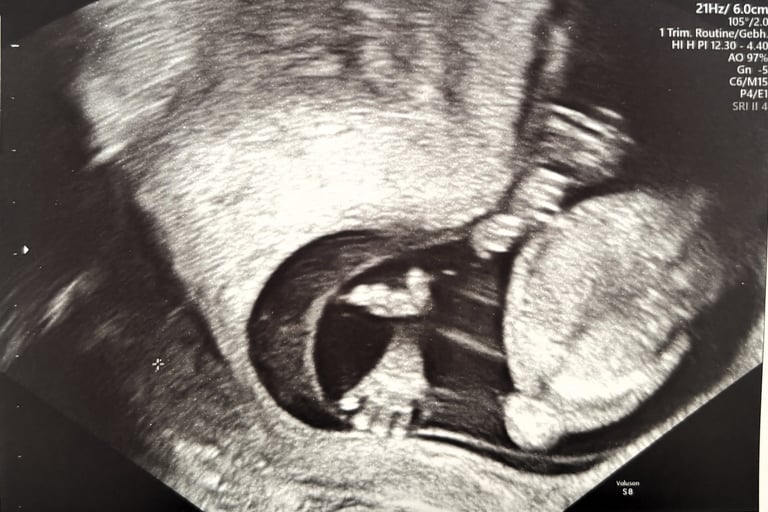

Today we had our third appointment with the gynecologist, and it was yet another exciting milestone for us. Your mother went through a test called NIPT, followed by another ultrasound. Today, I saw you for the second time.

The ultrasound image felt like a little greeting from you, as if you were saying hi to us from inside your mother’s womb. In that small, grainy photograph, you already felt so real, so close, and so deeply loved.